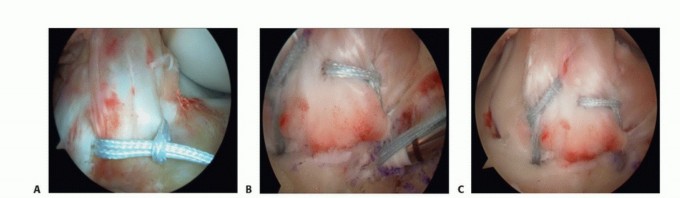

TECH FIG 2 • Arthroscopic screw fixation. A. The fracture fragment is maintained using Kirschner wire(s).

* B. A cannulated metal screw is inserted under fluoroscopic guidance. C. A resorbable screw in position. As resorbable screw are not typically cannulated, placement requires removal of the Kirschner wire. A second Kirschner wire maintains reduction while the resorbable screw is inserted. D,E. AP and lateral radiographs, respectively, showing the tibial spine fracture fixed with a single cannulated screw with washer. Care should be taken to avoid crossing the physis with the screw.

Once anatomic reduction of the fracture has been achieved, a 0.045-inch Kirschner wire is passed through the fracture fragment through the mid-parapatellar portal in the desired location of the final screw (TECH FIG 2A,B).

Metal or resorbable screws can be used for fixation (TECH FIG 2C).

With reduction maintained, the screw is gradually advanced under fluoroscopic guidance, making sure that the growth plate is not traversed.

AP and lateral radiographs of the knee are taken to document appropriate positioning of the screw and to document adequate reduction before closure (TECH FIG 2D,E).